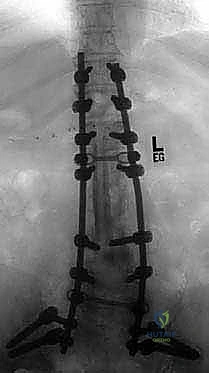

عملية دمج الفقرات (Spinal Fusion) هي إجراء جراحي يهدف إلى ربط فقرتين أو أكثر بشكل دائم، مما يزيل الحركة غير الطبيعية والمؤلمة بينهما، ويعيد الاستقرار الميكانيكي إلى العمود الفقري. في حالتنا هذه، يتم التركيز بشكل خاص على المنطقة الصدرية القطنية (Thoracolumbar Junction)، وهي المنطقة الانتقالية الحرجة التي تربط الجزء العلوي من الظهر (القفص الصدري الصلب) بالجزء السفلي (المنطقة القطنية المتحركة). يتم التثبيت باستخدام أدوات طبية معدنية متطورة (Instrumentation) مثل المسامير السويقية (Pedicle Screws) والقضبان المصنوعة من التيتانيوم.

السويقات الفقارية (Pedicles): دعامة التثبيت الأساسية والمحورية

تعتبر السويقة الفقارية (Pedicle) جسرًا عظميًا أسطوانيًا يربط الأجزاء الخلفية للفقرة (القوس الفقري) بالجسم الفقري الأمامي الضخم. في جراحة دمج الفقرات الحديثة، تعتبر السويقة نقطة التثبيت الرئيسية والأقوى للمسامير المستخدمة في العملية (Pedicle Screws). يختلف شكل وحجم وزاوية السويقات بشكل كبير على طول العمود الفقري، وفهم هذه الفروق الدقيقة أمر بالغ الأهمية للجراح لضمان وضع المسامير بأمان تام وفعالية قصوى دون الإضرار بالأعصاب أو الأوعية الدموية.